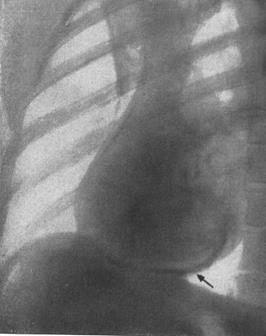

Рентгенологічно: тінь серця має широку основу і нагадує флягу, будинок з комином або шапку. Часто тінь серця досягає величезних розмірів (cor bovinum) без вираженого порушення скоротливої здатності серця. Іноді тінь серця набуває кулястої форми, утворюючи гострий кут з діафрагмою. Часто зліва є супутній плевральний випіт.

Рентгенологічно знаходять збільшені розміри тіні серця при відсутності ознак венозного застою у легенях.

Рентгенологічно знаходять значне збільшення тіні серця, дуги згладжені, пульсація серця ослаблена, ознаки застою в легенях слабо виражені.

Рис. 21. Констриктивний перикардит (" панцирне серце"). Звапнення особливо чітко помітні в базальних відділах (адаптовано за Р.Хеггліним, 1965).

Рентгенологічні зміни. Розміри серця не змінені або ж хіба що помірно збільшені. Часто спостерігається дилатація верхньої порожнистої вени, збільшення правого передсердя. Значно ослаблена пульсація серця. Патогномо­ніч­ною ознакою є звапнення перикарда у вигляді окремих вогнищ або ж обідка за контуром діафрагмальної і стернальної поверхні правого або лівого шлуночка, за винятком верхівки серця. Часом цей обідок є в ділянці атріовентрикулярного рівчака. У 60-90% таких хворих знаходять випіт в плевральній порожнині (гідроторакс). Не знаходять ознак застою в легенях.